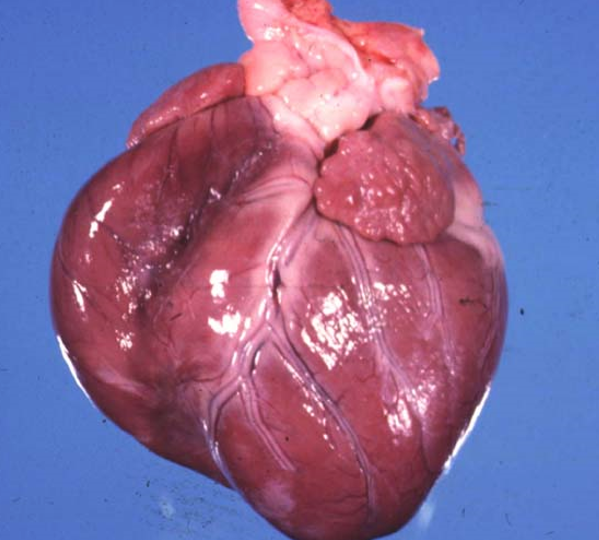

Καρδιά χοίρου

Ανθοκραμβοειδείς εκβλαστήσεις στο ενδοκάρδιο (χρόνια υπερπλαστική ενδοκαρδίτιδα) λόγω ερυθράς του χοίρου. Από Erisypelotrix

Διόγκωση της δεξιάς καρδιάς στο σκύλο. Διατατική μυοκαρδιοπάθεια